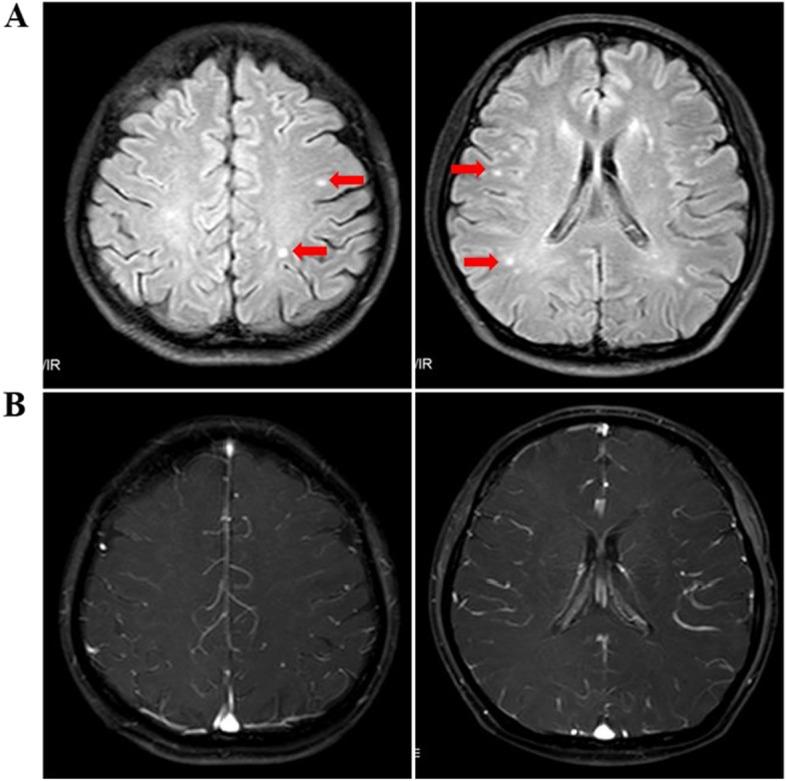

A 43-year-old female patient with advanced pancreatic ductal adenocarcinoma (PDAC) was treated with toripalimab in combination with gemcitabine and nab-paclitaxel (T-GA) as the first-line treatment. She developed immune-related encephalopathy with stuttering as the main clinical symptom and Magnetic resonance imaging (MRI) showed multiple cerebral white matter demyelination changes, concomitant with asymptomatic cardiac enzyme elevation and hypothyroidism. The symptoms resolved after the discontinuation of toripalimab and corticosteroid treatment.

一名 43 岁女性晚期胰腺导管腺癌(PDAC)患者接受 toripalimab 联合吉西他滨和 nab-紫杉醇(T-GA)作为一线治疗。她出现以口吃为主要临床症状的免疫相关性脑病,磁共振成像(MRI)显示多发性脑白质脱髓鞘改变,同时伴有无症状的心肌酶升高和甲状腺功能减退。停用 toripalimab 和皮质类固醇治疗后症状缓解。